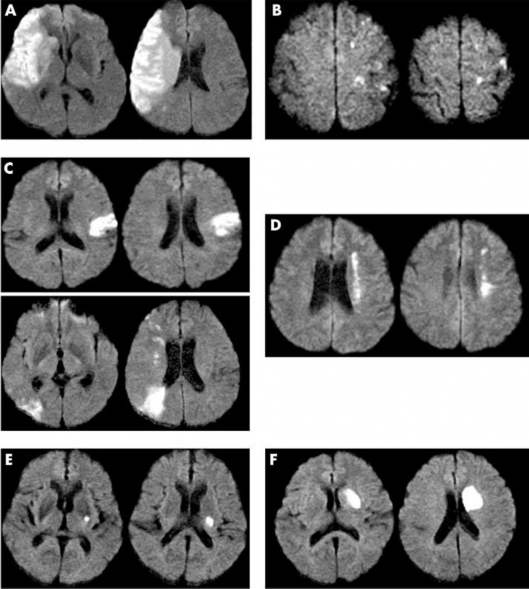

- Đánh giá tổn thương não trên hình ảnh học theo vị trí và kích thước tổn thương, gọi ngắn gọn là phân vùng nhồi máu của Bang (và cộng sự) [35]: năm 2005, Bang và cộng sự đã đưa ra phân loại tổn thương não theo phân vùng vị trí và kích thước tổn thương nhồi máu não, gồm sáu loại (hình 2.2).

(1) Nhồi máu não thùy ở từ hai phân vùng trở lên của vùng tưới máu động mạch não giữa

(2) Nhồi máu vỏ não khác: nhồi máu vỏ não ở 1 phân vùng hoặc ở vùng ranh giới vỏ

(3) Nhồi máu nhỏ vỏ não: nhồi máu vỏ nhiều ổ nhỏ (<1cm) hoặc nhồi máu một hoặc nhiều ổ ở trung tâm bán bầu dục

(4) Nhồi máu vùng ranh giới sâu (sang thương dạng chuỗi nhiều múi, nằm riêng lẻ hoặc nối với sang thương thể vân, nằm ở vùng trên hoặc cạnh não thất)

(5) Nhồi máu sâu nhỏ

(6) Các nhồi máu sâu khác: nhồi máu lớn ở vùng thể vân bao trong (sang thương

>15mm), hoặc có thêm sang thương ngoài vùng thể vân-bao trong.

Hình 2.2. Phân vùng tổn thương não theo Bang. (A) Nhồi máu não thùy, (B) Nhồi máu nông nhỏ, (C) Nhồi máu não nông khác, (D) Nhồi máu ranh giới sâu, (E) Nhồi máu não sâu nhỏ, và (F) các nhồi máu sâu khác. “Nguồn: Bang OY, 2005”[35]

Bang và cộng sự ghi nhận cách phân loại này có thể giúp tiên đoán sớm kết cục chức năng và tái phát của bệnh nhân nhồi máu [35].

Từ cách phân loại này, chúng tôi điều chỉnh tên gọi và thứ tự để dễ sử dụng hơn, gồm sáu loại như sau:

(1) Nhồi máu nông nhỏ: nhồi máu nhiều ổ nhỏ ở vỏ não hoặc nhồi máu một hoặc nhiều ổ ở trung tâm bán bầu dục.

(2) Nhồi máu sâu nhỏ.

(3) Nhồi máu một vùng vỏ: nhồi máu một phân vùng ở vỏ não hoặc nhồi máu vùng ranh giới vỏ não.

(4) Nhồi máu ranh giới sâu

(5) Nhồi máu sâu lớn: nhồi máu vùng sâu kích thước >1,5cm hoặc có kèm nhồi máu ngoài vùng đậu vân

(6) Nhồi máu diện rộng (thùy): nhồi máu rộng từ hai phần đến toàn bộ vùng tưới máu động mạch não giữa (phân vùng sâu, vùng tưới máu nhánh nông trên, vùng tưới máu nhánh nông dưới).